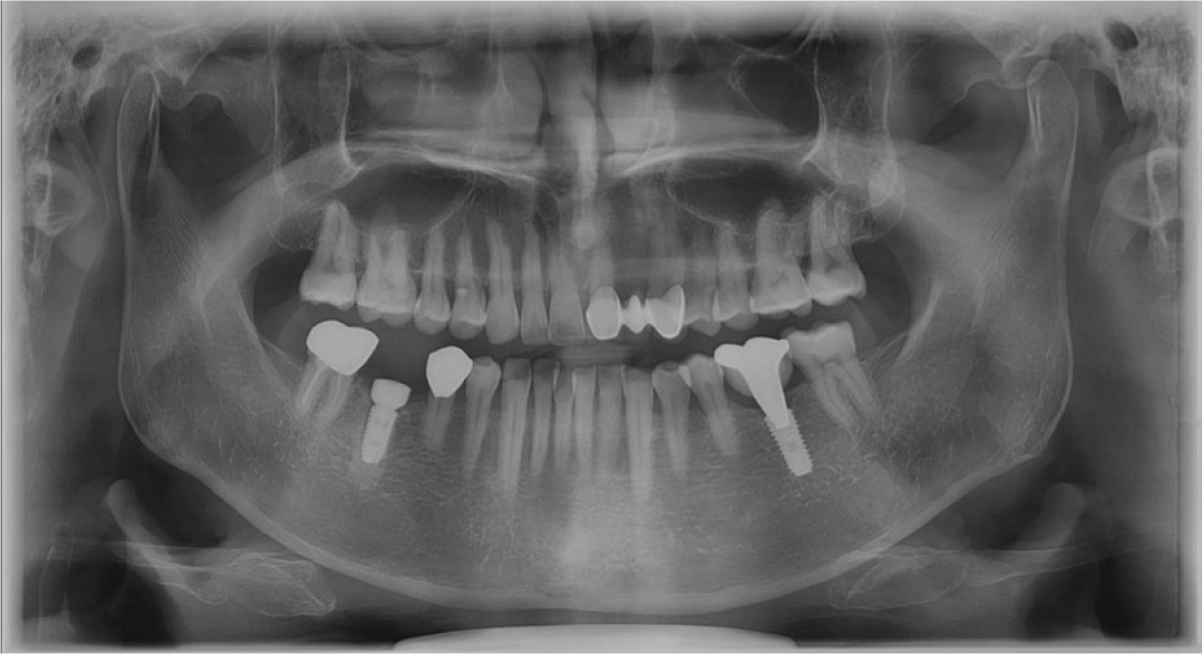

An implant of 5.0 mm diameter and 10.0 mm length (Luna®; Shinhung, Seoul, Korea) was placed at the lower right 1st molar site, and the implant stability quotient (ISQ) was 81. The Φ6.0 × 5.0 mm healing abutment was placed and sutured with 4-0 Supramid® (Assut Medical Sarl, Pully-Lausanne, Switzerland) (Fig. 11). It showed stability on the post-operative panoramic radiograph (Fig. 12). After 4 months, the final prosthesis was completed (Figs. 13 and 14).

At 5 years follow-up, the implant showed stable alveolar bone without any signs of peri-implantitis or bone resorption on the radiograph analysis (Figs. 15 and 16). In addition, there was no bleeding on probing and no clinical problems.